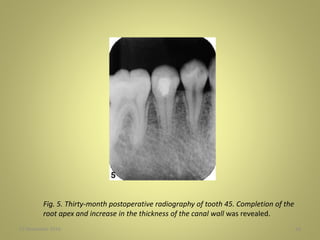

Fig. 5. Thirty-month postoperative radiography of tooth 45. Completion of the

root apex and increase in the thickness of the canal wall was revealed.